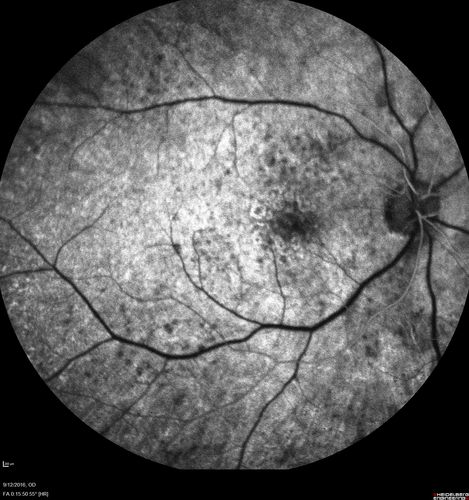

Syphilitic Chorioretinitis

Severe outer retinal atrophy and RPE non-geographic atrophy from syphilis.  Vision improved from 20/63 to 20/32 with therapy.  Images look a lot like DUSN.  Patient had several surgeries (vitrectomy for floaters, vitrectomy for macular pucker, Avastin injections and macular laser for edema) prior by other retina specialists prior to being correctly diagnosed and treated.